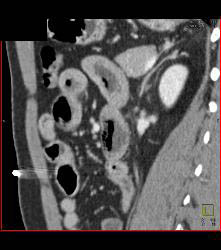

Superior Mesenteric Artery (SMA) Syndrome With Gastric Outlet Obstruction